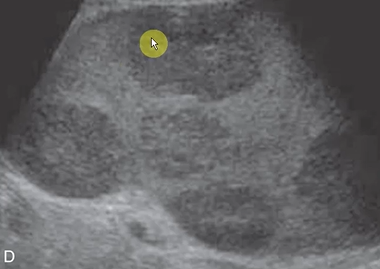

Transverse or long view?

Transverse